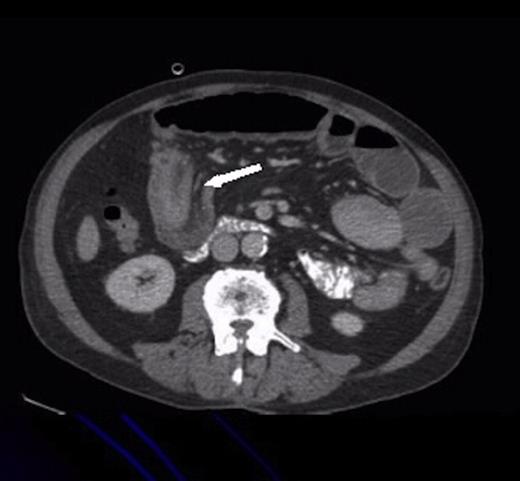

Two weeks later, he was readmitted with worsening pain and absolute constipation. Abdominal X-ray showed marked dilatation of the proximal and mid small bowel loops in keeping with high grade small bowel obstruction. CT confirmed this, demonstrating the classic donut sign on coronal reformat; the wall of the intussusception appeared thickened but no definite mass lesion was seen at this point.

Sagittal CT showing the ‘sausage’ appearance of the intussusception